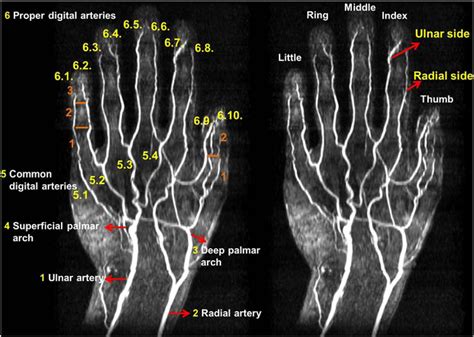

Understanding the intricacies of an MRI of hand can provide valuable insights into various hand conditions and injuries. Magnetic Resonance Imaging (MRI) is a powerful diagnostic tool that uses magnetic fields and radio waves to produce detailed images of the body's internal structures. When it comes to the hand, MRI scans offer a non-invasive way to visualize bones, muscles, tendons, ligaments, and other soft tissues with exceptional clarity.

An MRI of hand is a specialized imaging technique that focuses on the structures within the hand. This procedure is particularly useful for diagnosing conditions that affect the bones, joints, and soft tissues of the hand. Unlike X-rays, which primarily show bone structures, an MRI provides a comprehensive view of both hard and soft tissues, making it an invaluable tool for orthopedic and rheumatologic evaluations.

• Detailed Images: MRI provides high-resolution images of both hard and soft tissues, allowing for a comprehensive evaluation.

• mri anatomy of the hand